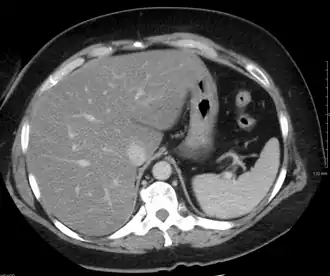

Tomografia computadorizada de abdômen com fígado gorduroso.

As análises de sangue que traduzem o funcionamento do fígado revelam apenas ligeiras alterações inespecíficas. O diagnóstico será feito com exames que permitam visualizar o fígado, como a ecografia ou a tomografia computorizada, que evidenciam um excesso de gordura no fígado. O diagnóstico confirmatório é feito com a realização de uma biopsia hepática (do fígado), sendo positivo caso mais de 10% da sua massa seja gordura, porém esta confirmação não é, geralmente, necessária.[7]